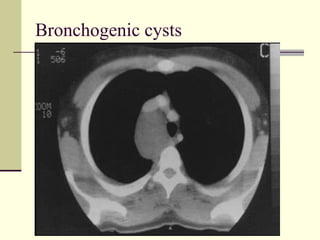

Middle Mediastinal Masses   1. Lymphadenopathy  2. Aneurysms  3. Esophageal duplication 4. Bronchogenic cysts

Bronchogenic cysts

• 68.